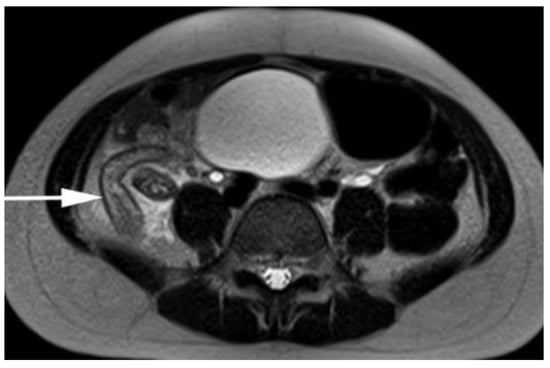

- Moore, M.M.; Kulaylat, A.N.; Brian, J.M.; et al. Alternative diagnoses at paediatric appendicitis MRI. Clin Radiol. 2015, 70, 881–889. [Google Scholar] [CrossRef]